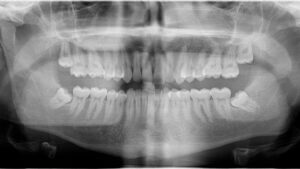

A continuación os dejamos el plan de tratamiento interdisciplinar y el programa de mantenimiento periodontal, llevados a cabo durante la fase correctora-rehabilitadora y tras la finalización del tratamiento,

Como hemos mencionado en artículos anteriores, los dientes incluidos son aquellos que se quedan dentro de los maxilares porque no logran su erupción completa en